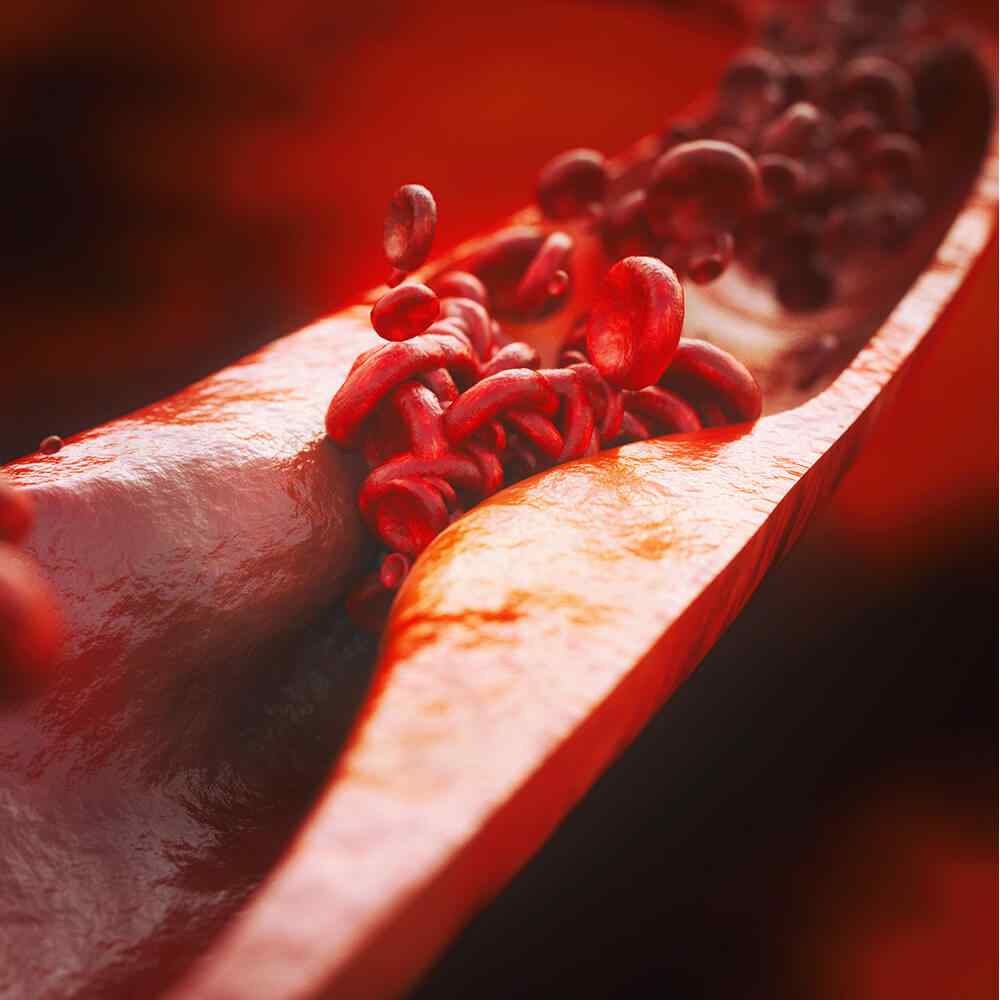

Atherosclerosis

Atherosclerosis is thickening or hardening of the arteries caused by a buildup of plaque in the inner lining of an artery. Can cause a heart attack, stroke, aneurysm, or blood clot.

Atherosclerosis is the buildup of fats, cholesterol and other substances in and on your artery walls. This buildup is called plaque. The plaque can cause your arteries to narrow, blocking blood flow. The plaque can also burst, leading to a blood clot.